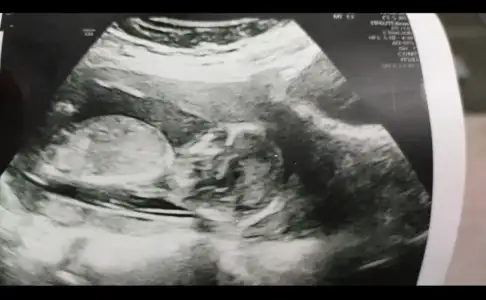

Tek yumurta sanırım ama boyutsuz USG paylaşın benim ikiz kızlarım var 💗💗🥰🥰

Çift yumurta dedi doktorumuz ama bilemiyorum ikiz olduğuna soktayım hala😬 yaa normal ultrasonu almayı unutmusum heyecandan ayrıntılı olanlar var ama 10haftalık var onu paylaşıyorum anlasılır belki😇 ne güzel ikiz kız bakımında zorlandınızmı😅😇 bende ilk hamile olduğumu öğrendiğimde kız hissediyordum ama ikiz olunca bir kız bir erkek gibi geliyor ama gönül öyle istiyor diyede olabilir🙈 sağlıklı olsunlar da ama bi merak oluyor illa işte😊

Eklentiler

• IMG_20200924_131022.webp

IMG_20200924_131022.webp

31,3 KB · Görüntüleme: 56

İkiside kız görünüyor ama bu haftalar yanitir siz 11 12 13 haftalar paylasin